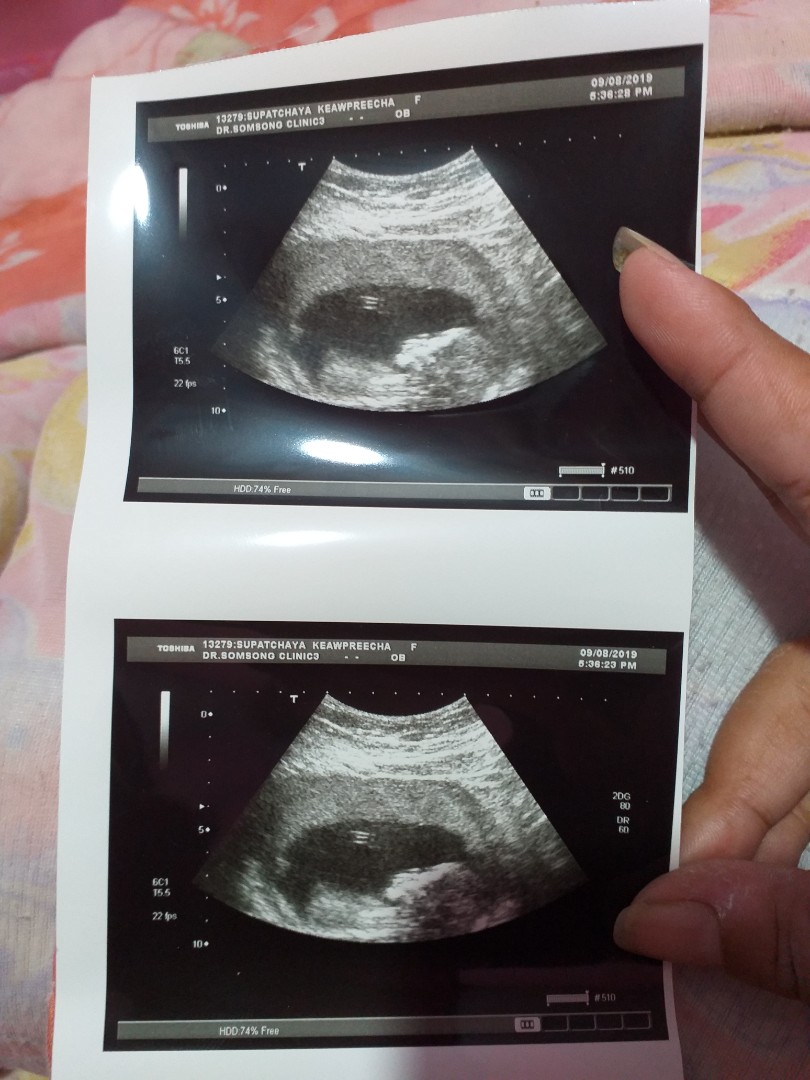

รูปแรกตอนเจอน้อง 13w ตอนนี้22Wค่ะ